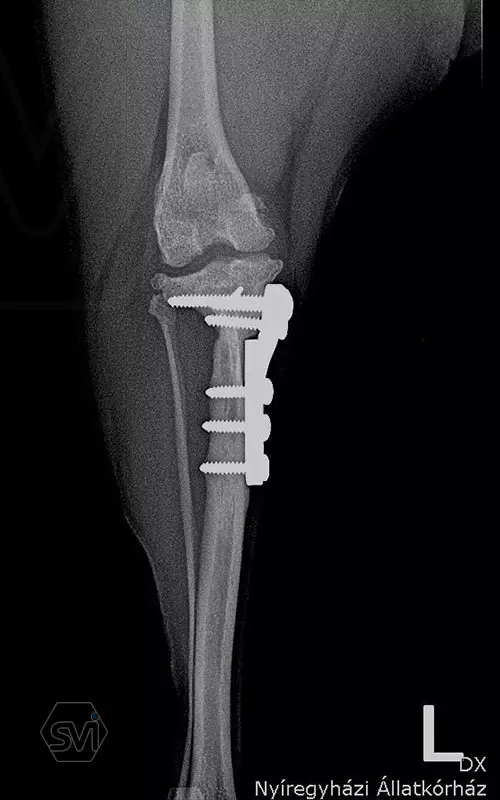

The attached x-rays were taken during the check-up of a 6.5-year-old Yorkshire terrier that underwent TPLO-M surgery a year and a half ago, the limb is fully loaded, it shows no lameness, the osteotomized parts are well ossified, the bone stock has not been resorbed.

A mellékelt képek egy másfél évvel ezelőtt TPLO-M műtéten átesett, most 6,5 éves yorkshire terrier kontrollja során készült, a végtagot teljesen terheli, sántaságot nem mutat, az oszteotomizált részek jól csontosodtak, a csontállomány nem szívódott fel.